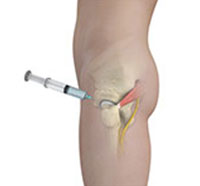

Hip joint injections involve injecting medicine directly into the hip joint to diagnose the source of pain or treat pain due to conditions such as arthritis, injury or mechanical stress of the hip joint. Hip pain may be experienced in the hip, buttock, leg or low back.